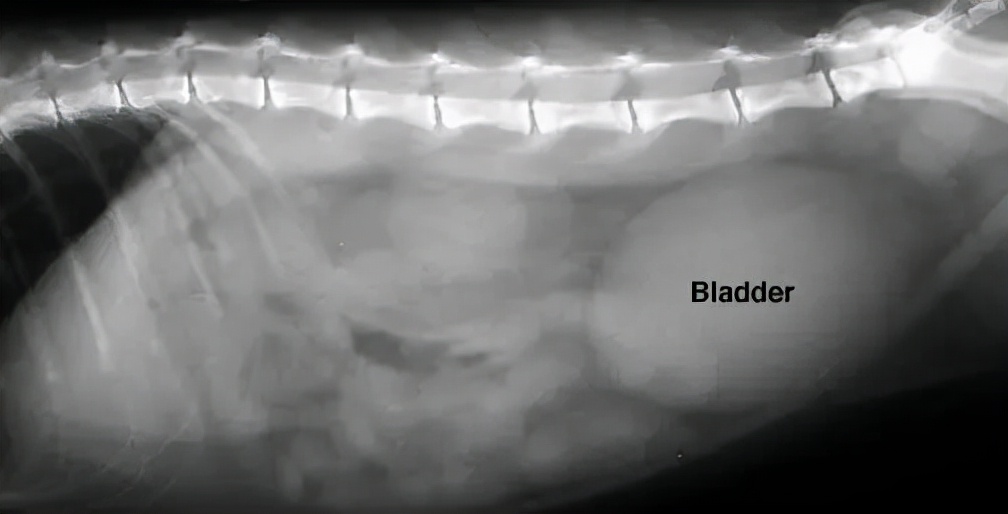

通常建议进行血液学检查(血常规、血液生化)和尿液检查,来帮助寻找尿道阻塞的原因,而X线和B超能帮我们判断是否有尿结石、尿结晶或尿道栓子。

↑图片右侧的的椭圆形影像是一个充盈的膀胱

对于小猫咪来说,最重要的是尽快恢复尿道通畅。